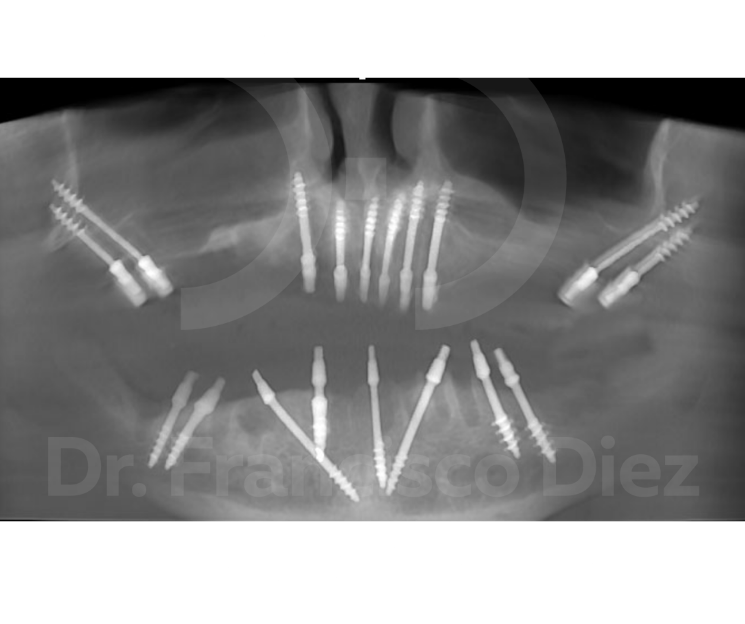

Frente a este panorama, existe una solución diferente: los implantes monofásicos corticobasales de carga inmediata. Su gran ventaja es que no requieren regenerar hueso. Trabajamos con el hueso basal, el que siempre está ahí, sin necesidad de incisiones complejas. En una sola intervención mínimamente invasiva favorecemos la curación y el crecimiento óseo. Y lo más importante: en 24 horas el paciente puede volver a comer cómodamente y a sonreír con confianza, sin inflamación, sin dolor y con un postoperatorio casi inexistente.

Pero esta solución no está al alcance de cualquier profesional. Solo los dentistas que dominan las técnicas avanzadas en implantología pueden ofrecer resultados inmediatos para todos los pacientes, incluso los más complejos, y resolver los problemas que la implantología convencional no puede.